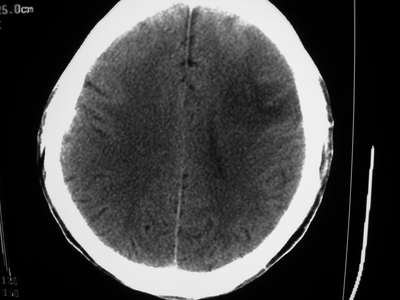

以下是引用卜一在2007-1-19 15:29:00的发言:[br]治疗前:1月14日右侧额叶皮质下低密度影,而治疗后:1月18日右侧阴影消失,新近出现左侧额叶侧脑室前角旁大片状低密度影,边缘模糊。支持—双侧额叶后部缺血性脑梗塞。